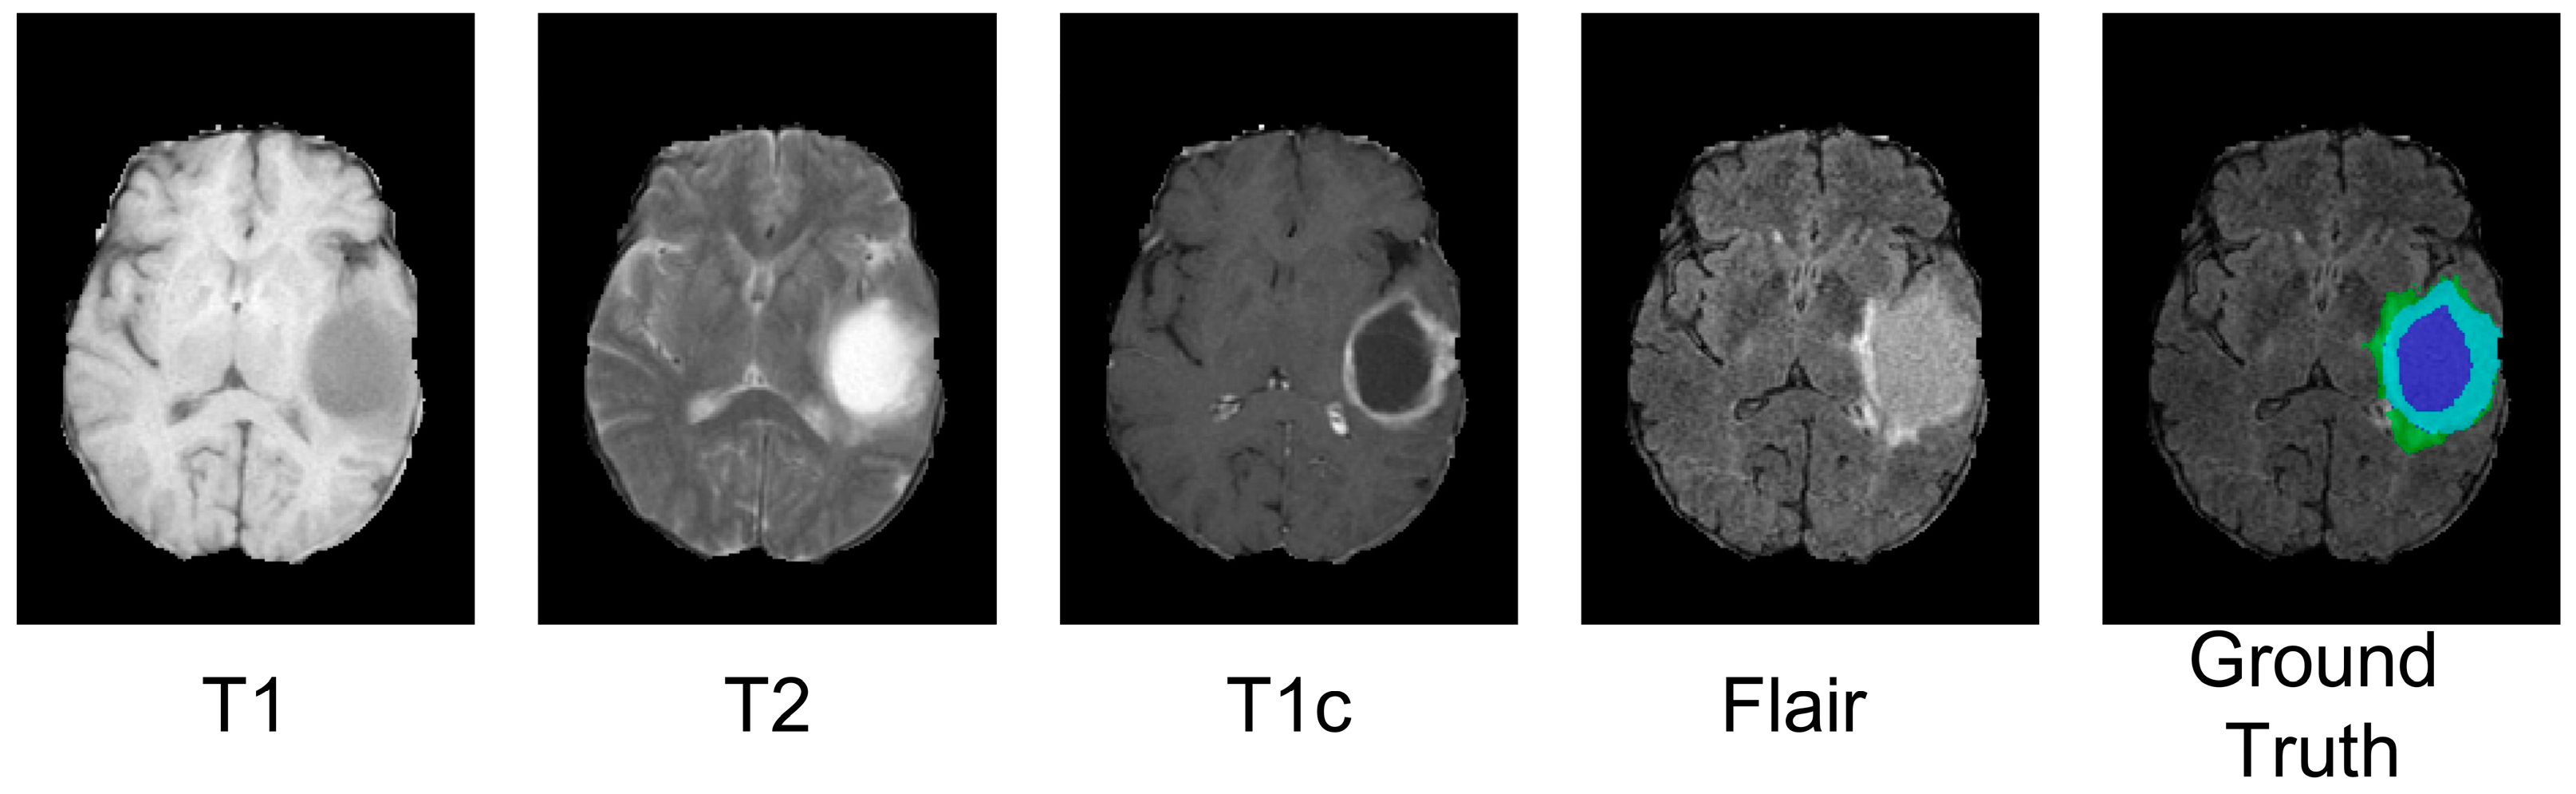

3.5.1. Datasets and Pre-Processing